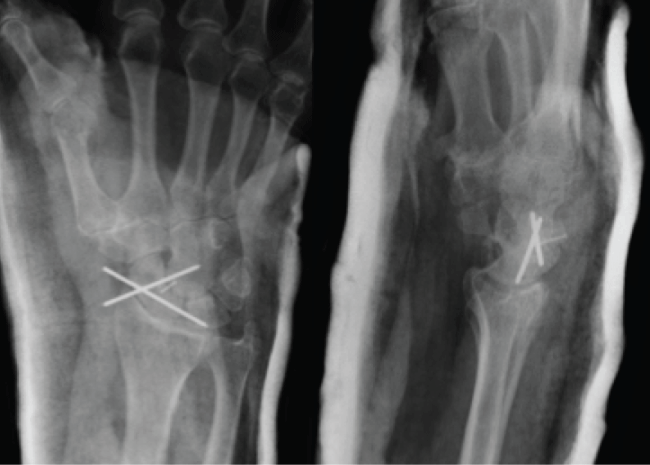

A 76 year old right hand dominant male retired anaesthetist presented with a painful and swollen right wrist after falling from standing height, landing on the ulnar aspect of his out stretched right hand. The injury was closed and the limb was neurovascularly intact. He had a previous distal radius fracture years ago previously treated non-operatively. Wrist radiographs demonstrated an isolated scaphoid dislocation (Figure 1). Further imaging with computer tomography (CT) was considered, however as the patient presented after hours a CT scan would have delayed access to the operating room. At this time we had enough information from emergency department radiographs to proceed with a closed reduction and the use of fluoroscopy in the operating room provided the information required to proceed to an open scapholunate repair.

The patient was transferred promptly to the operating room. Once anesthetized a closed reduction was performed to reduce the dislocated scaphoid. Image intensifier revealed an increased scapholunate interval and no perilunar instability. A decision was then made to perform an open repair of the scapholunate ligament. A dorsal approach to the wrist with a Berger capsulotomy was performed. The Scapholunate ligament had avulsed off the scaphoid and there was a bone fragment large enough to place a 1.2 mm screw to hold the S-L ligament in addition to through bone sutures, K-wires were also used to stabilize the Scaphoid (Figure 2).